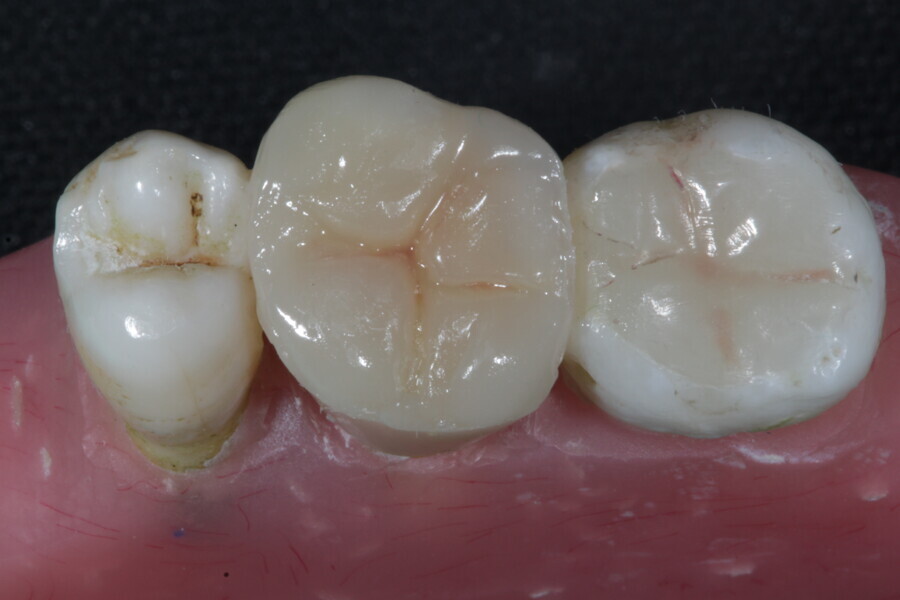

1. direct restoration using a fibre-reinforced flowable composite and membrane cube after endodontic treatment (Figs. 21–35); and

1. restoration reinforcement of a vital tooth with a fibre-reinforced flowable composite and membrane (Figs. 36–45).

Example 3—Restoration reinforcement of a vital tooth with a fibre-reinforced flowable composite and membrane.